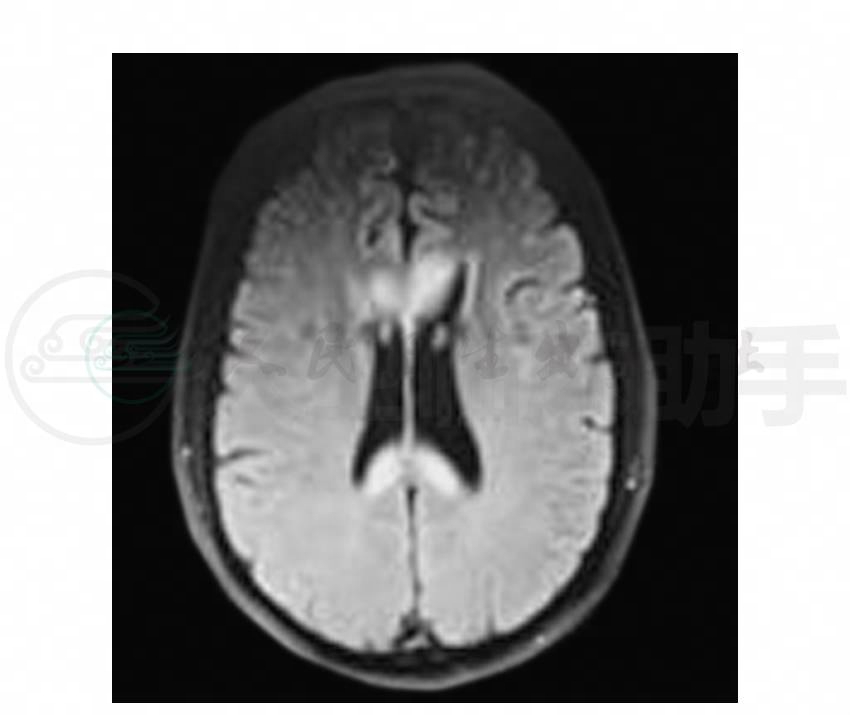

6.头颅MRI(2011-2-15)DWI:胼胝体弥漫高信号,T2WI:未见明确出血灶,胼胝体见多发片状高信号,FLAIR呈高信号,增强后病变强化不明显,余未见异常。诊断:胼胝体脱髓鞘改变,酒精中毒可能,请结合临床(图1~图4)。

图2 头颅MRI轴位FLAIR示胼胝体斑片状高信号